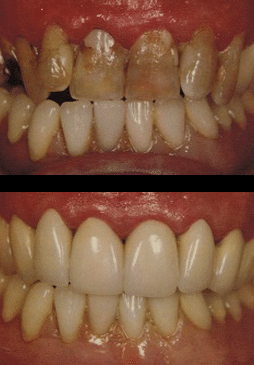

Before & After

Replacing a single tooth with a single tooth implant does not endanger the health of the neighboring teeth. Because a dental implant will replace your tooth root, the bone is better preserved. Dental implants integrate with your jawbone, helping to keep the bone healthy and intact. Several missing teeth can also be replaced with individual implants. This method will place a dental implant at the site of each missing tooth, providing ideal replicas of your lost teeth. Multiple teeth may also be restored with an implant bridge, which is a prosthetic comprised of three or more crown units, depending upon the number of missing teeth.